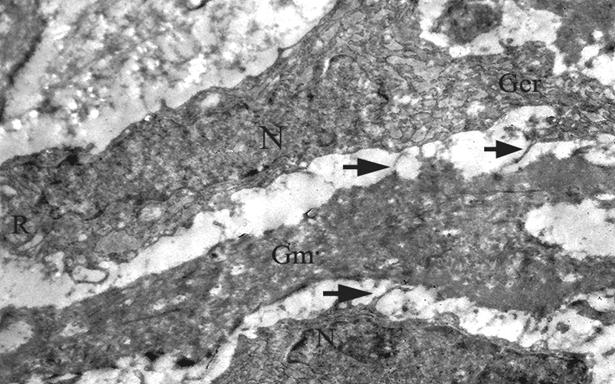

Figure 6

Residual β-TCP bone graft material is seen between two osteoblast cells of the periosteum, note the cytoplasmic processes (arrows) extending from the cell membrane to the bone graft substitute. This electron micrograph was taken from the β-TCP + HBOT group which were sacrificed at one week time point (TEM×7500) (N; Nucleus, R; Ribosome, Ger; Granular Endoplasmic Reticulum).

The ultrastructural findings in the Control + HBOT and B-TCP + HBOT (Figure 6) groups were similar to their non-HBO counterparts with the exceptions of dominant cell types and collagen structure at the early stages of healing. Our observations at one week specimens revealed that the chondroblasts had become scarce and they were mainly replaced by highly active osteoblasts that contain well-developed intracytoplasmic organelles. Additionally, the collagen fibrils appeared to be more organized in bundles. On the other hand, HBOT did not seem to have an effect over the periosteal cell structure of the CPCBB group (Figure 7 a and b) as the cellular degeneration findings were still clearly visible at all time points (Figure 8).